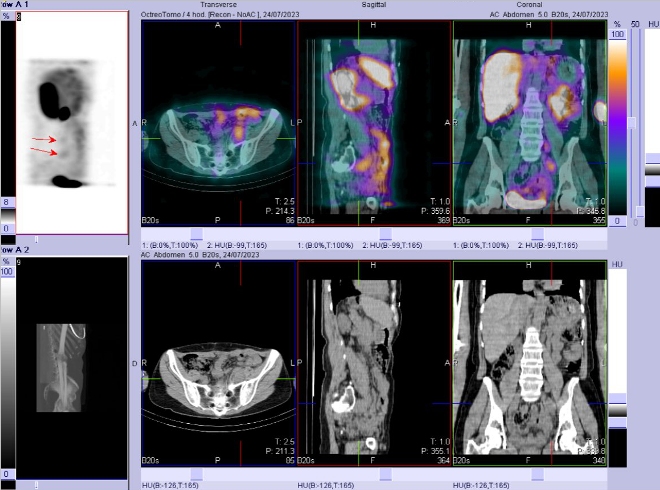

/ Obr. č. 1: Celotělová scintigrafie v přední a zadní projekci a SPECT/CT břicha a pánve 4 hod. po aplikaci OctreoScanu./

/ Obr. č. 2: SPECT/CT břicha a pánve 4 hod. po aplikaci OctreoScanu.

Pozorujeme patologicky zvýšenou depozici radiofarmaka:

- málo kontrastně ve většině LU formujících paket v retroperitoneu paraaortálně vlevo až podél ilického svazku v pánvi vlevo (největší LU podél a. iliaca externa vel. 25x26 mm). Ojedinělé uzliny z tohoto paketu jsou bez zvýšené depozice radiofarmaka

- mírně pruhovitě v jizvě po laparotomii - v. s. hojivé změny.

Akumulace v játrech, žlučníku, ledvinách, močovém měchýři a střevních kličkách představuje fyziologickou distribuci.

U 61leté ženy s neuroendokrinním tumorem sestupného tračníku jsme scintigraficky prokázali zvýšenou denzitu somatostatinových receptorů ve většině paketujících LU v retroperitoneu paraaortálně vlevo a podél ilického svazku v pánvi vlevo - odpovídá přítomnosti nádorové tkáně (NET), nález relativně málo kontrastní, menší část uzlin s nízkou/bez zvýšené akumulace radiofarmaka.